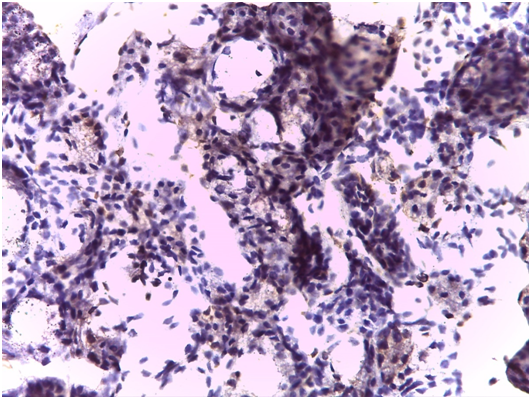

Immunohistochemical findings

As regards to immunohistochemistry (IHC), all cases of GBS have expressed focal positivity that ranged from moderate (++) to strong expression (++++) for CD68 (Figure 7) and CD16b (Figure 8). These cases have revealed a natively strong immunoreactivity for CD34 (Figure 9). The twelve cases showed negative expression for cathepsin-K. By contrast, the representative slides of both SS and normal mucosa did not display any significant immunoreactivity for the above mentioned immunohistochemical markers. To contrast, the main histological and immunohistological findings were compiled in Table 2.

Figure 7 Expression of CD68 in the salivary glandular tissue (Original magnification 40x).